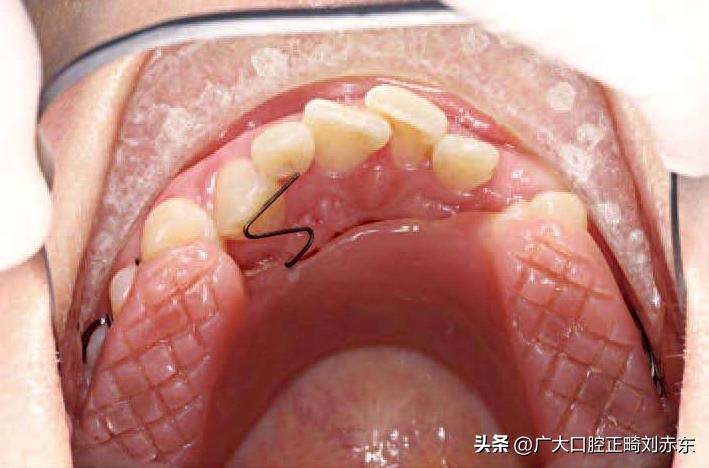

图为控根移动

图为使用活动矫治器,间歇式施加矫治力